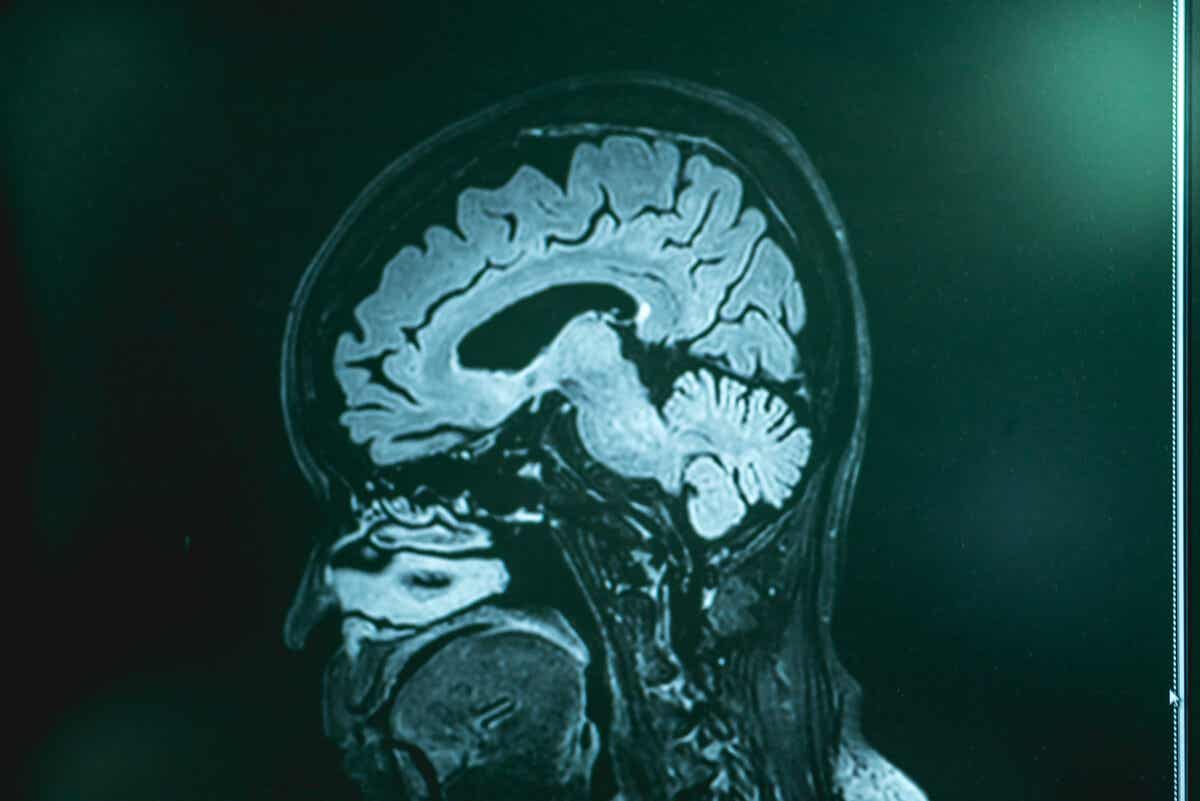

Wie in den MSD-Manuals angegeben, lässt sich eine primäre Amöben-Meningoenzephalitis nur durch eine Lumbalpunktion (mit anschließender Liquoranalyse) sowie durch eine Hirnbiopsie bestätigen. Ärzte führen diese Tests bei Personen durch, die Symptome einer Naeglereiasis aufweisen und in den letzten Tagen mit unbehandeltem Süßwasser in Kontakt gekommen sind.

Bildgebende Untersuchungen (Computertomographie und Magnetresonanztomographie) hingegen weisen die Krankheit nicht nach. Dennoch lassen sich dadurch andere mögliche Gesundheitsprobleme ausschließen. Nach der Gewinnung des Liquors führen die Ärzte Kulturen oder genetische Analysen durch, um das Amöbengenom zu finden.